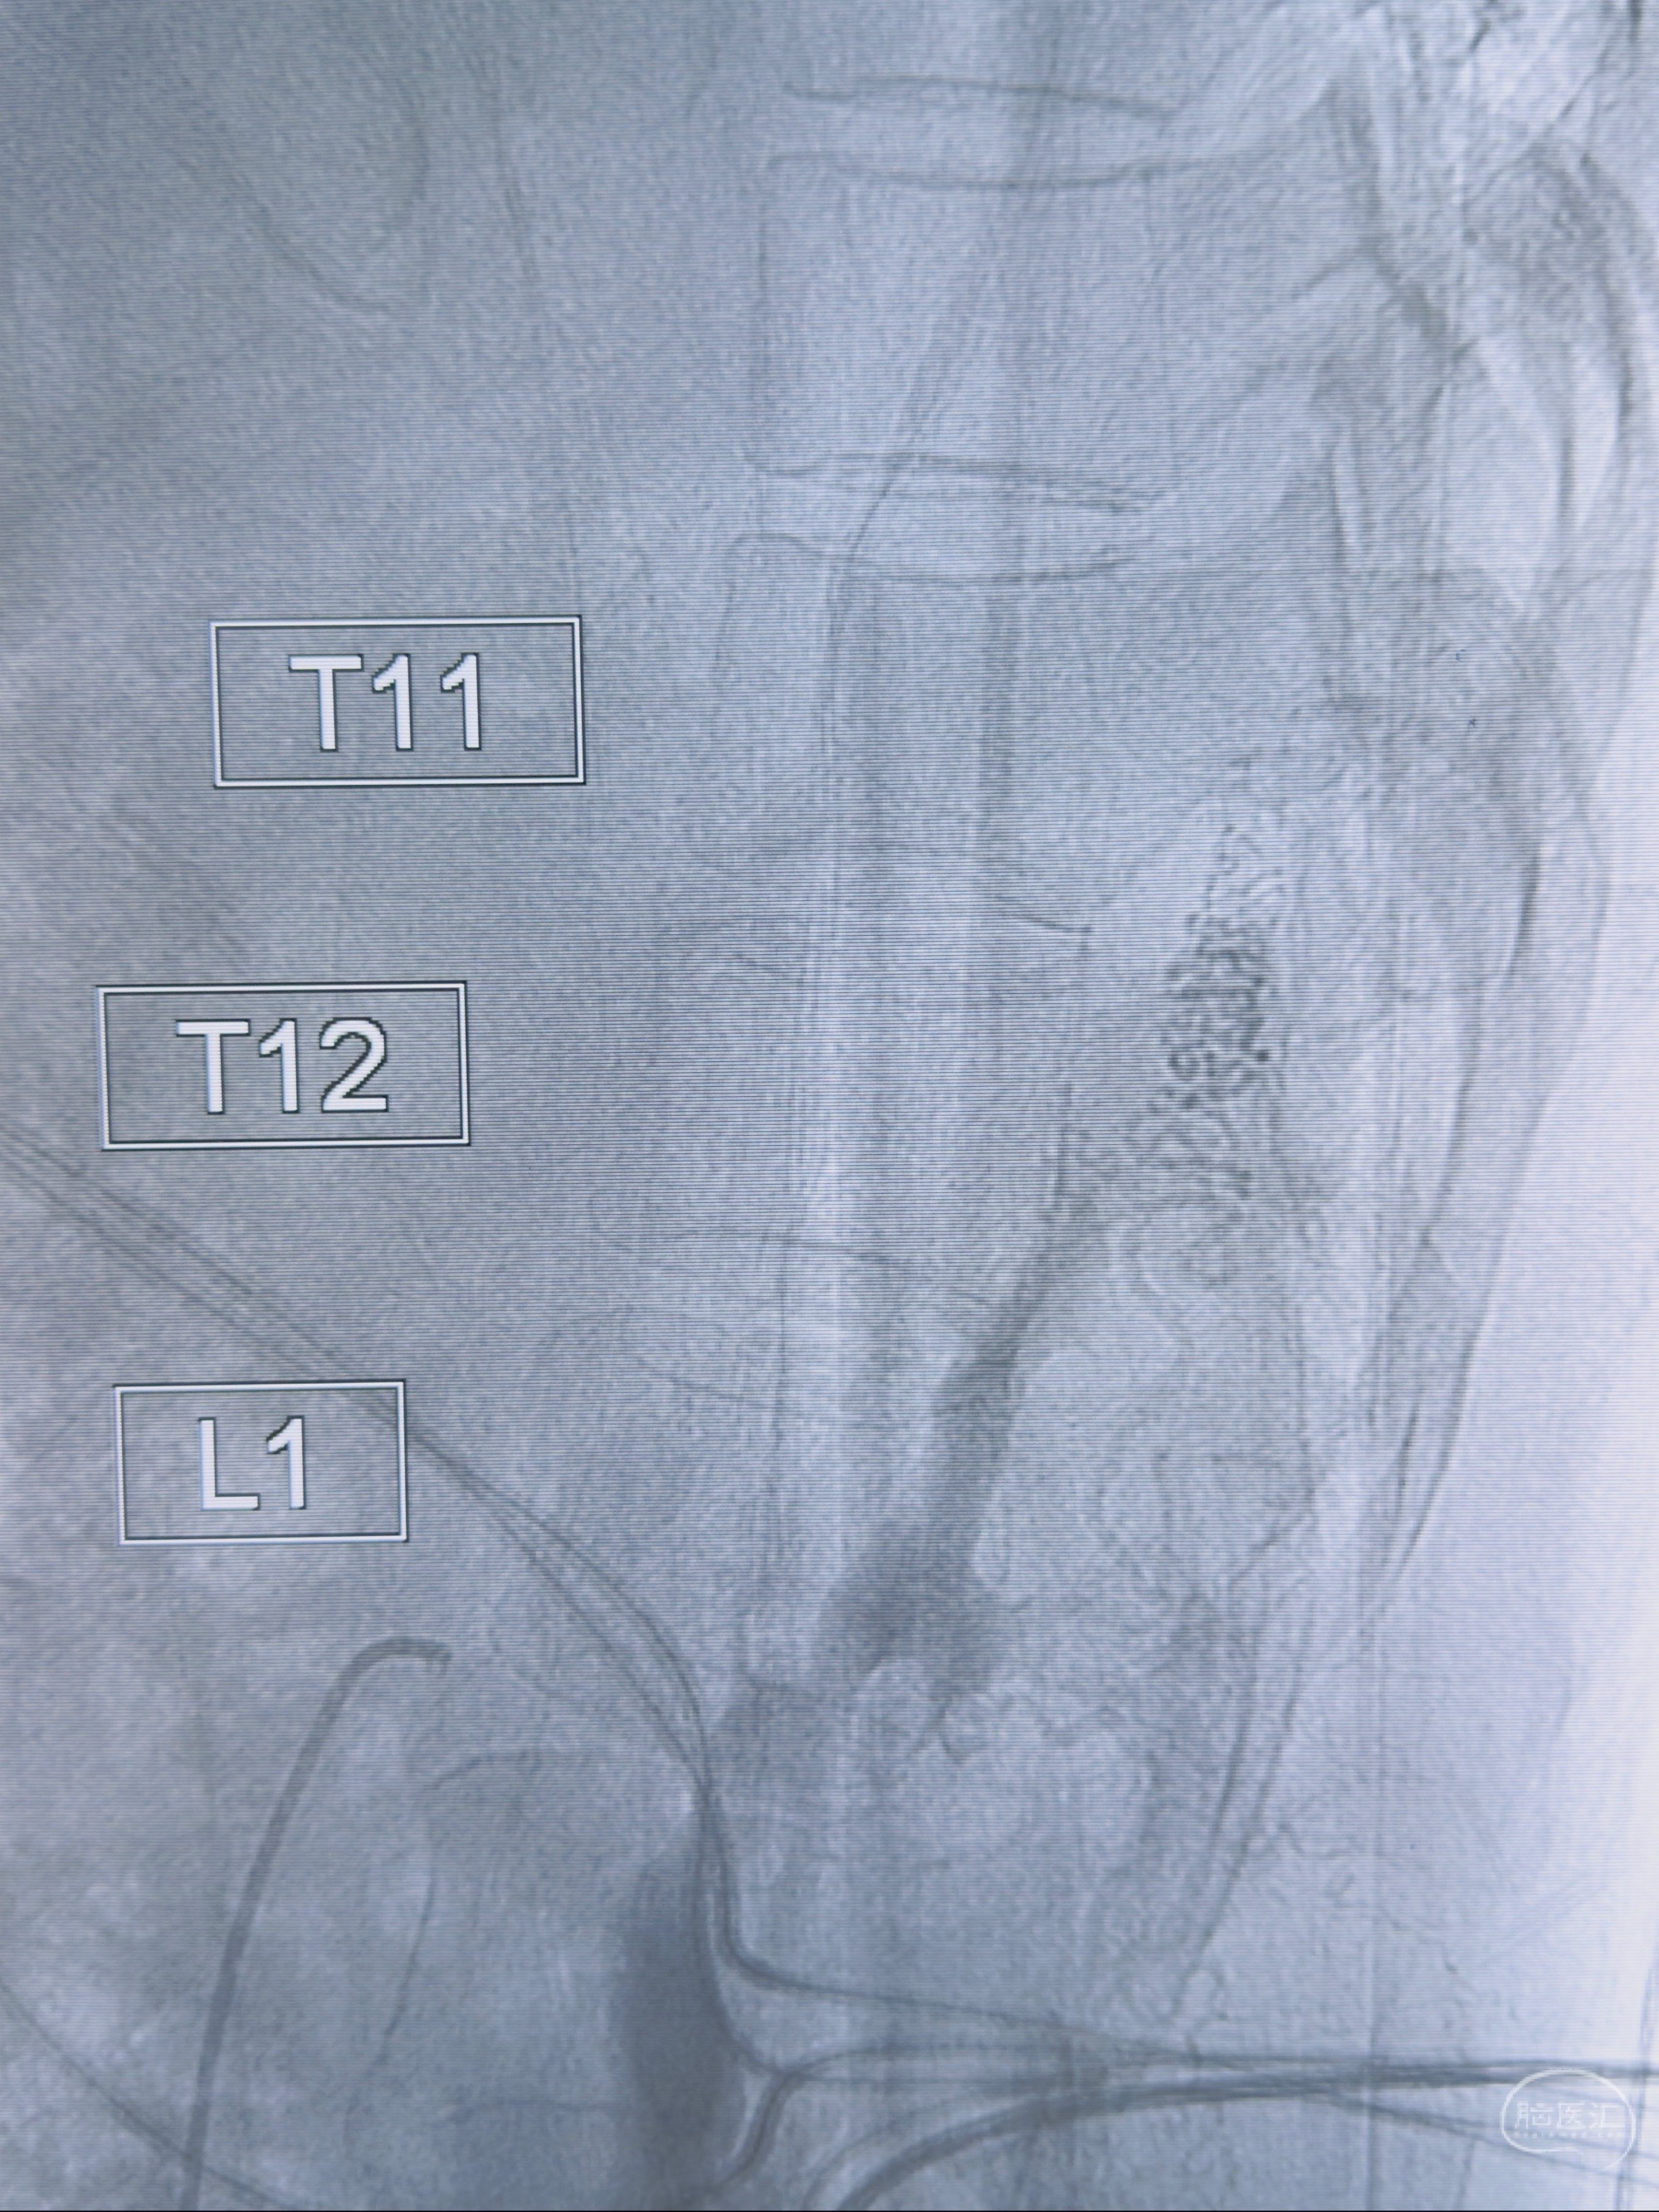

2023-10-13DSA:右侧L1水平硬脊膜动静脉瘘,供血动脉为右侧L1,附近动脉未见明确吻合供血,供血动脉处可见脊髓前动脉发出

1.建议外科手术,已行美兰定位c